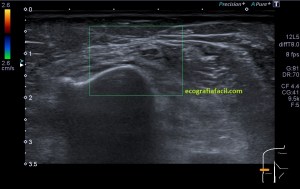

En este breve post te voy a presentar unas imágenes muy bonitas de una vesícula, en una paciente que acude a la cita de ecografía por sospecha de patología a ese nivel, con molestias anodinas e inespecíficas en el contexto de un estudio de su especialista de digestivo.

Observa las imágenes y luego te explico los hallazgos:

Cuando hice el corte longitudinal de la vesícula pude ver hasta tres patologías distintas, una adeomiomatosis (sin artefacto en cola de cometa), una litiasis vesicular y barro biliar, 2,3 y 4 respectivamente.

La adenomiomatosis, como un aumento de la ecogenicidad y el tamaño de la pared vesicular, la litiasis como una estructura hiperecogénica con sombra acústica posterior y el barro biliar, hiperecogénico rellenando toda la estructura ovoidea de la vesícula.

El cuello vesicular estaría afectado por la adenomiomatosis, el cuerpo por la litiasis y el barro ocuparía el fundas vesicular.